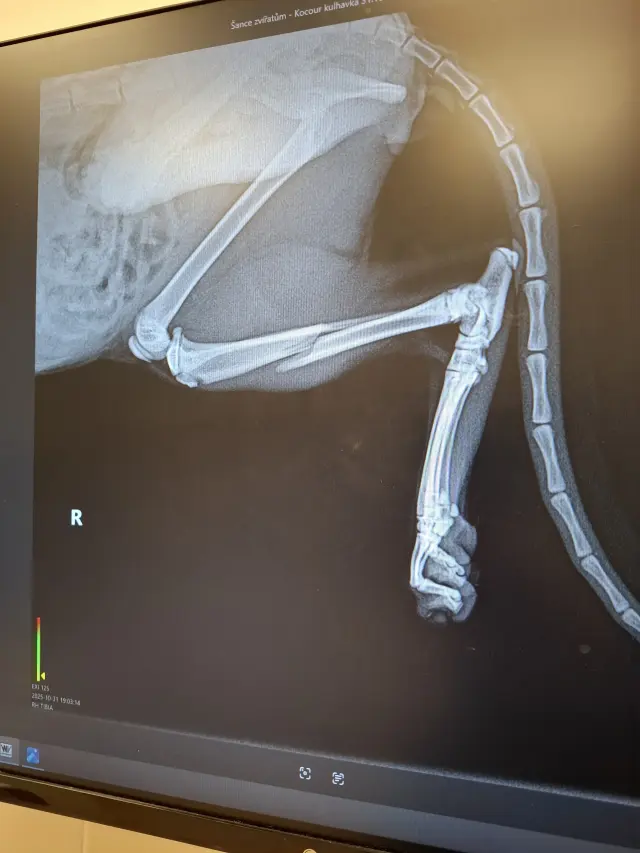

Fotogalerie